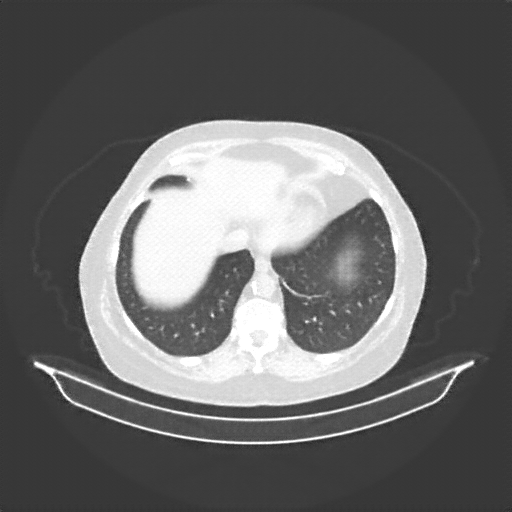

Reconstructed NATIVE CT scan (cycle consistency)

No window - Raw intensity values

Lung window (WL -600, WW 1500 β†’ Low βˆ’1350, High +150)

Mediastinum window (WL 40, WW 400 β†’ Low βˆ’160, High +240)